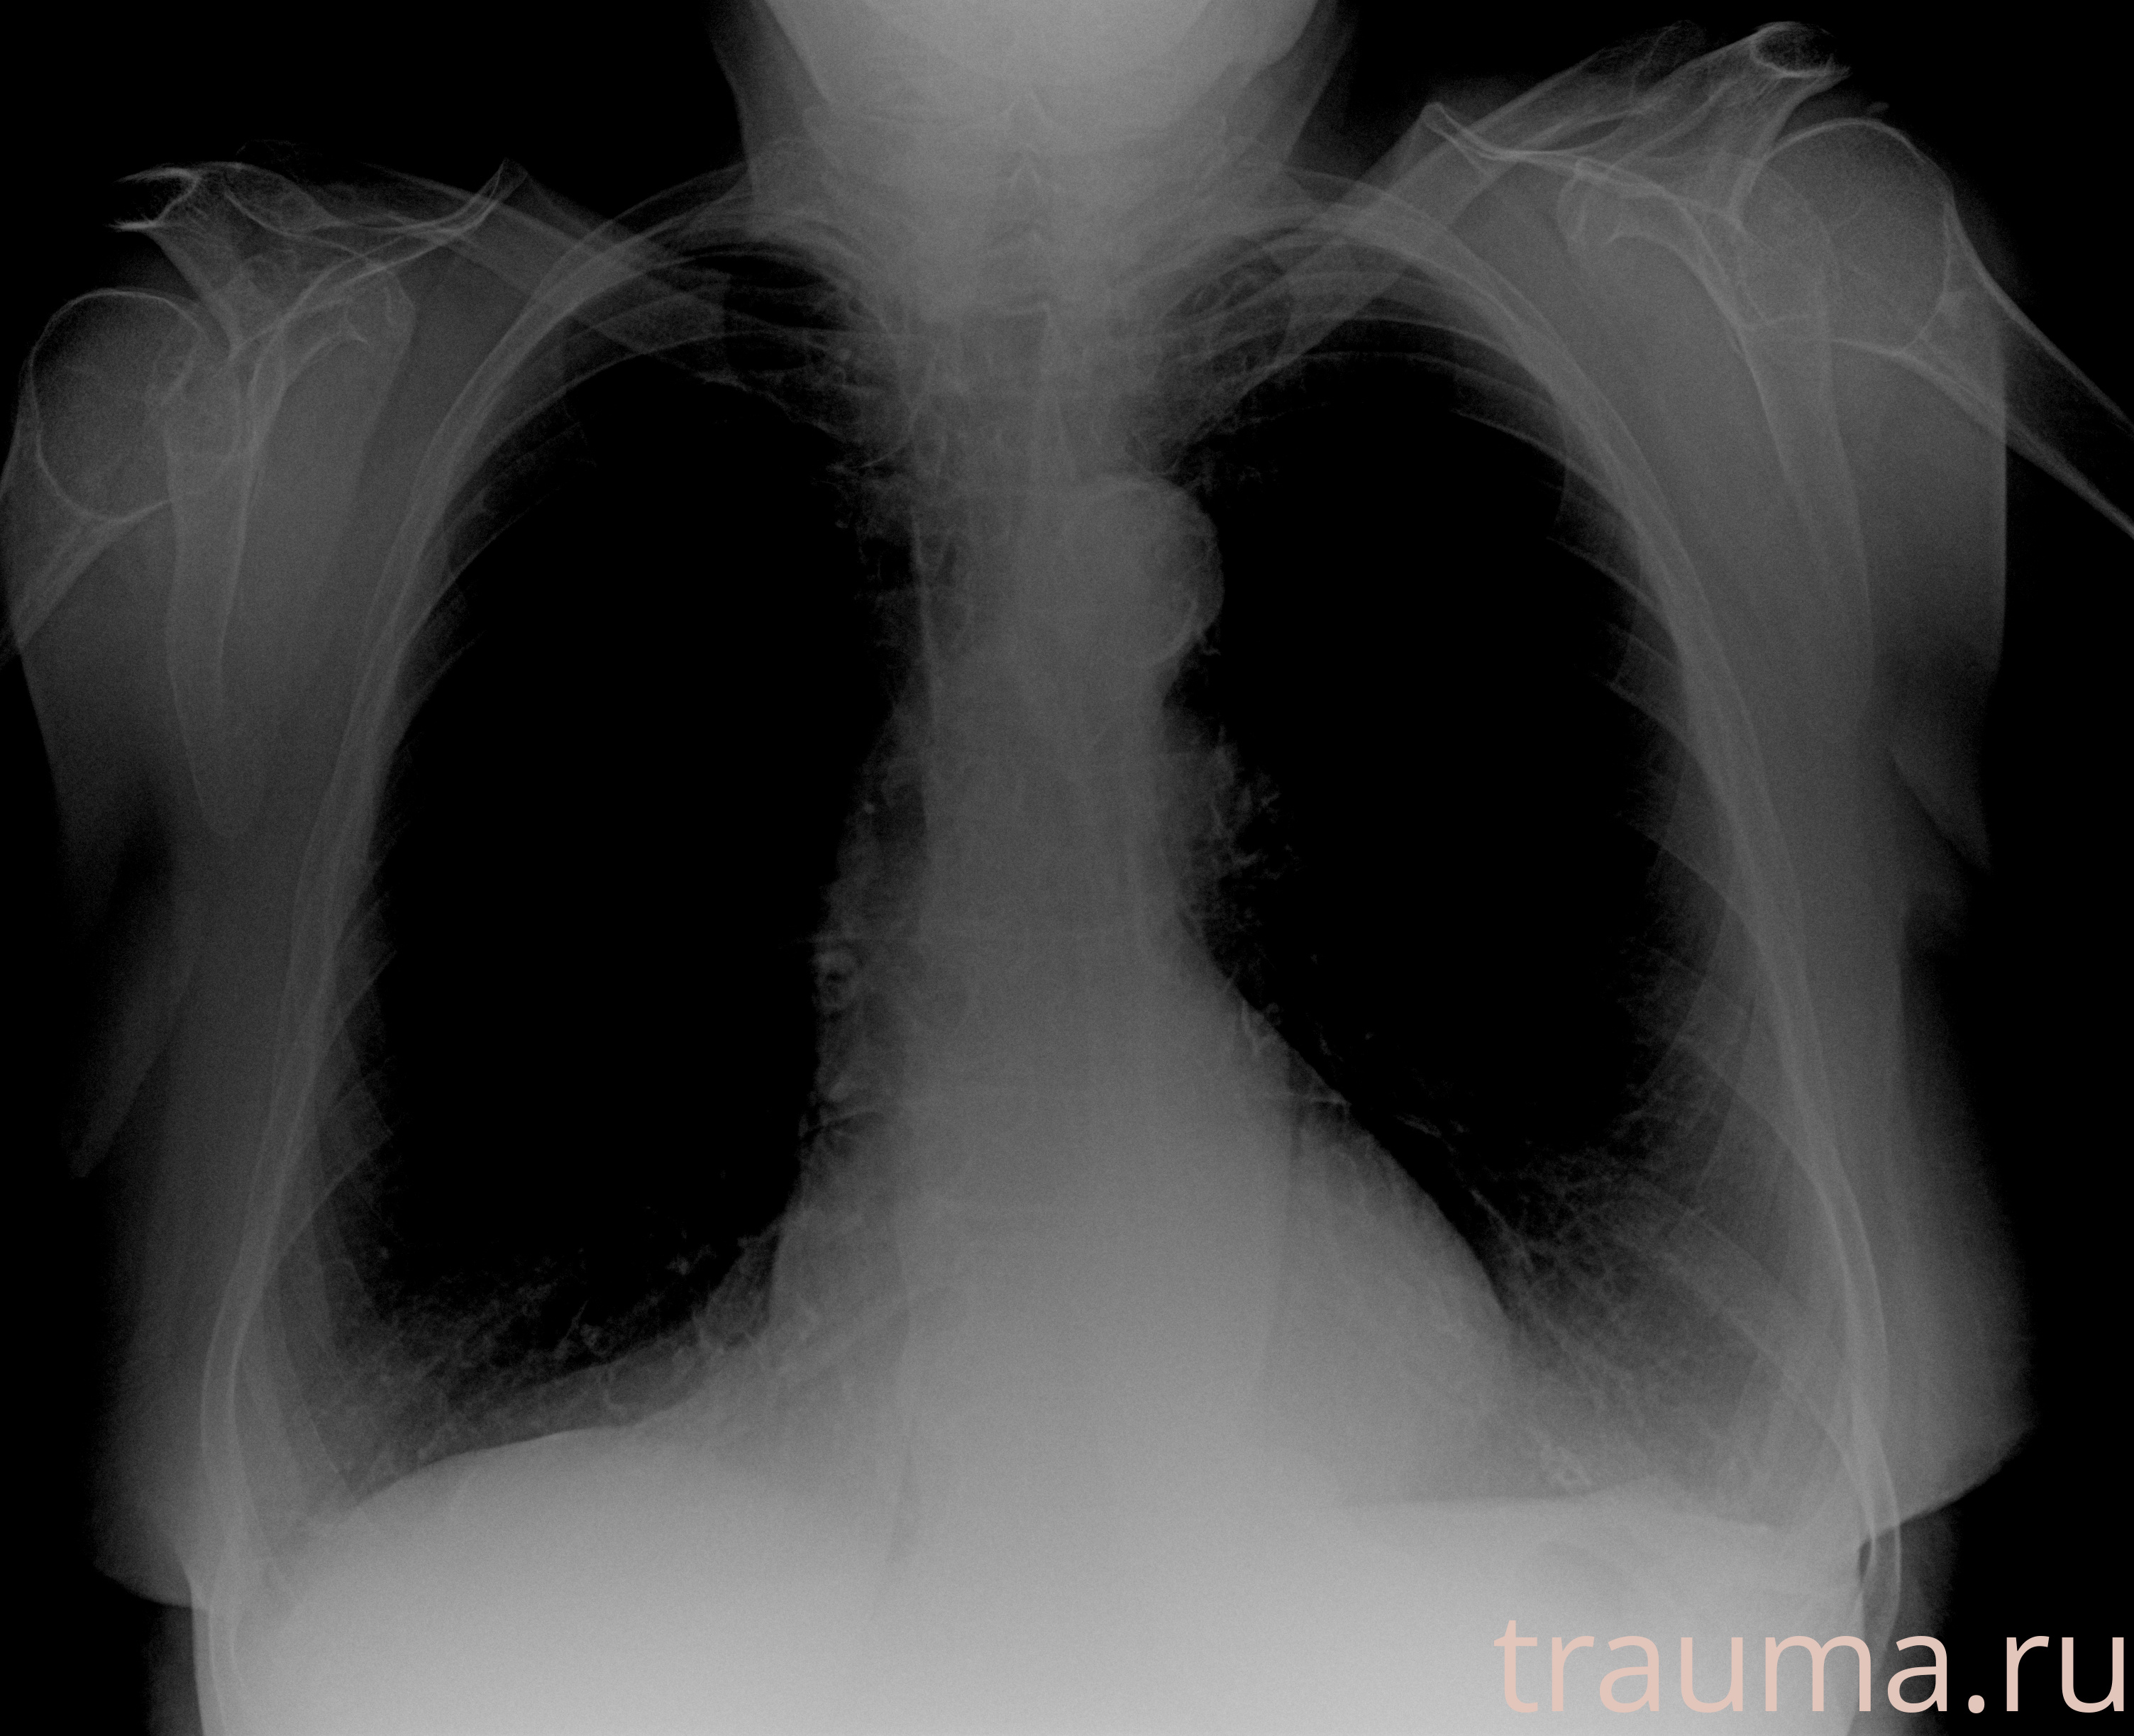

Рентгенограммы

Рентген на дому: по вашему адресу приезжает врач-рентгенолог, травматолог-ортопед с мобильным рентгеновским аппаратом, проводит диагностику травмы или заболевания, делает необходимые рентгенограммы, дает рекомендации по дальнейшему лечению. Получить качественные снимки в домашних условиях возможно благодаря уникальной методике, разработанной МосРентген Центром для института  Склифосовского

Яркость: 1   Контраст: 1   Инвертировать: 0 Увеличение: 1

Перетаскивайте мышь вверх/вниз для контраста, влево/право для яркости. Прокрутка колесом изменяет масштаб. Нажмите Сбросить для возврата к исходному изображению. При увеличении держите мышь в той области, которую хотите рассмотреть.